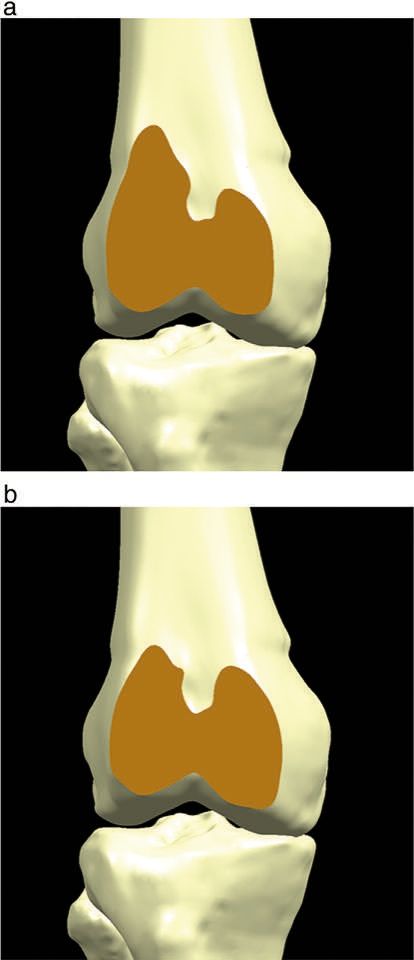

A patellofemoral arthroplasty maybe performed through any of the standard surgical approaches used for total knee arthroplasty such as midvastus and subvastus as well as parapatellar approaches. Importantly for PFA (patellofemoral arthroplasty) is the early activation of the vastus medialis obliques (VMO). This leads to early stabilization of the patella and the feeling of patient security. Many patients may well have laxity of the MPFL which may be deficient or pathologically lax. Some surgeons prefer a lateral approach in order to preserve any fibres remaining of the MPFL. However in terms of patella height unlike tibial TKA patients, PFA patients often have thin or deficient lateral patellae and reestablishing normal patella height with a polyethylene prosthesis will lead to tightening of the lateral soft tissue, particularly in absence of trochlea component external rotation. Here the surgeon should be aware that if a medial approach is used, a titrated lateral release or step cut lengthening of the iliotibial band and the capsule as well as the lateral patellofemoral ligament maybe required. Whereas lateral release is rarely required in modern total knee arthroplasty, the nature of the pathology and isolated patellofemoral disease should be in the mind of the operating surgeon as some form of lateral retensioning may be necessary. The majority of the patella implants are dome or oval dome rather than anatomically shaped. Therefore if a natural patella is resurfaced with a dome the resultant implant may cause tilting (figure 1). Therefore close observation of the lateral soft tissues is essential as tightening of the lateral capsule may be caused by inattention to patella resurfacing. Alternatively in the past the patient may have had an overzealous lateral release which may require retensioning or repair by the surgeon.

The patella preparation is performed first to allow easier displacement of the patella into the lateral gutter without the need of eversion. This relieves the pressure on the soft tissues. The patella synovium and fat are cleared back so the surgeon can see the patella tendon and the quadriceps tendon attachment sites. These form the basis of the patella cut which may be situated here or using a caliper, an appropriate cut made be made to replicate the thickness of a polyethylene dome. Removal of the synovium and fat and scar tissue around the patella circumference greatly aids mobilization of the patella. Some surgeons feel this also deinervates the patella, but the nerve supply of the patella is unclear and the use of this circumcision of the patella is mainly in my view, to allow mobilization more effectively and more accurately placed patella cut. The patella remnant should have a minimum of twelve millimeters of bone to avoid the possibility of patella fracture at a later time. A surgeon should check that once the patella cut is made and the dome has been prepared, the thickness of the patella at the apex should match exactly the thickness of the native patella prior to preparation. My belief is that the positioning of the patella prosthesis should be apex led, that is the apex of the polyethene dome should occupy exactly the position of the patients apex of the native patella. This way no additional stress within in the soft tissues is introduced as the apex cannot be misplaced. Some patella systems have a inset patella with a milling system allowing the polyethene to beinserted within the bony shoulders of the remaining patella. These implants particularly should be orientated to match the patient’s own native apex position.

This debate is a continuation of the discussion between TKA surgeons and the developing thoughts of PFA surgeons regarding trochlea component orientation. TKA methods call for a balanced flexion and extension gap which as indicated above, are tied to a tibial cut perpendicular to the long axis. To compensate for the natural tibial plateau varum, the femoral component is externally rotated when the knee is flexed to 90°. It is often taught that the aim in TKA is the ‘the grand piano’ sign that is produced when the anterior cut is at 3° of external rotation (2)The grand piano sign is consistently produced when surgeons use this technique to cut 3° of external rotation relative to the posterior condyle access or by resection parallel to the surgical epicondylar access (figure 4a). The butterfly sign (figure 4b) is produced by resection with 0° of external rotation relative to the posterior epicondylar axis (3).